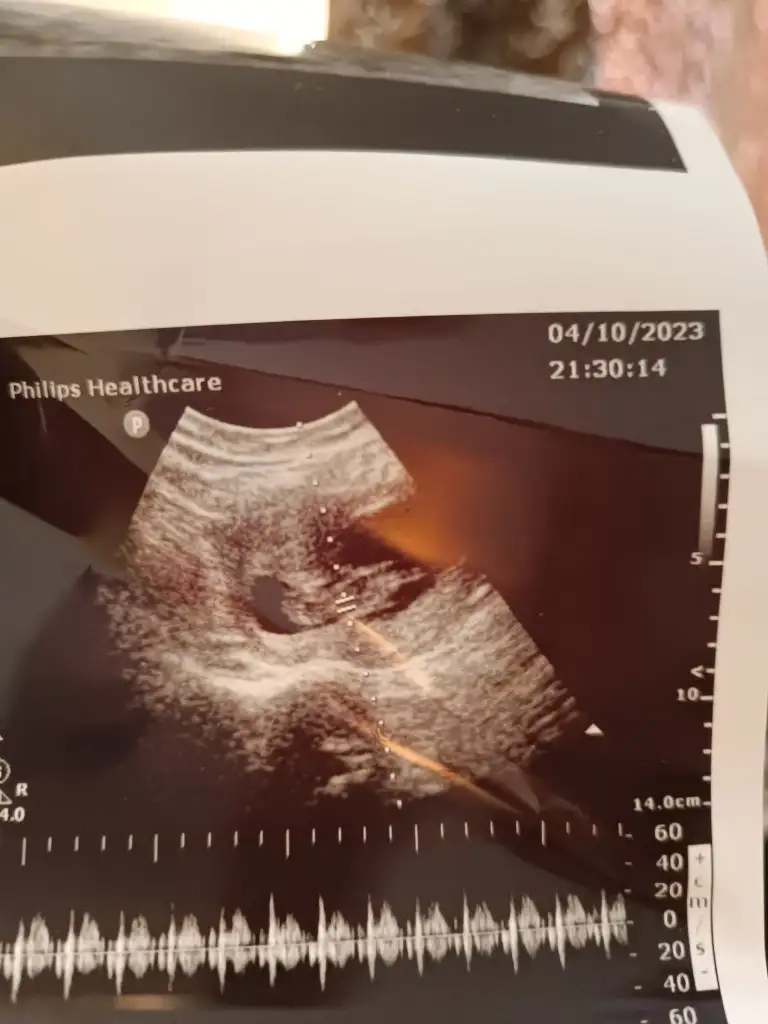

Arkadaşlar bana da bir yorum yapabilir mısınız lütfen? 12 hafta kız, 17 hafta da erkek dedi doktorum. Yanılmış olabilir mi?